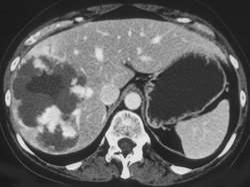

男,46岁,右上腹胀痛不适2月余,请结合CT图像,选择最可能诊断 ( )A、肝囊肿B、肝转移癌C、肝血管瘤D、肝脓肿E、肝癌

问题 男,46岁,右上腹胀痛不适2月余,请结合CT图像,选择最可能诊断 ( )

选项 A、肝囊肿 B、肝转移癌 C、肝血管瘤 D、肝脓肿 E、肝癌

答案 C